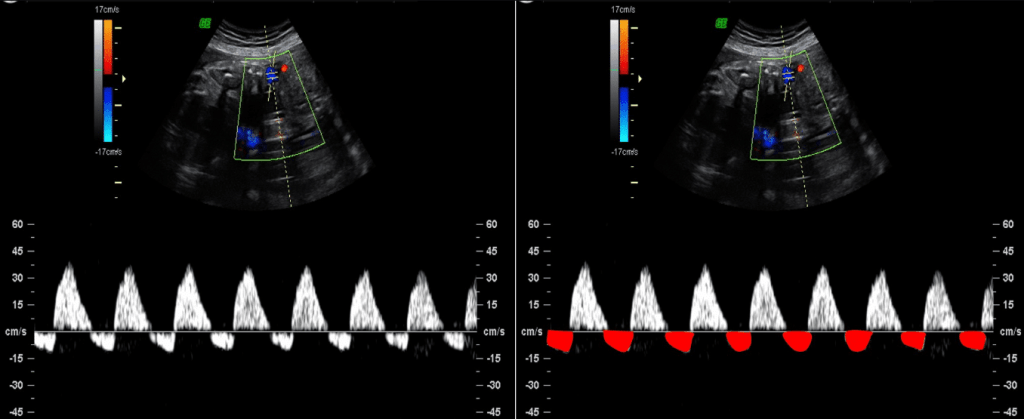

Predição de pré-eclâmpsia e restrição de crescimento fetal

Por fim, o Doppler das artérias uterinas avalia o compartimento materno da placenta, fornecendo informações sobre a resistência vascular uterina e o funcionamento das artérias espirais.

Durante a gestação normal, a invasão trofoblástica no primeiro trimestre promove o remodelamento dessas artérias, o que, consequentemente, reduz sua resistência e garante suprimento adequado à placenta. No entanto, alterações nesse processo, como resistência aumentada ou presença de incisura diastólica bilateral, estão associadas a um maior risco de pré-eclâmpsia (PE) precoce e restrição de crescimento fetal (RCF).

Nesse contexto, utiliza-se o índice de pulsatilidade (IP) das artérias uterinas para quantificar essa resistência, sendo valores elevados indicativos de risco aumentado.

Além disso, a presença de incisura protodiastólica sugere fluxo mais restrito, e seu achado precoce no primeiro trimestre pode ajudar na triagem de gestantes de alto risco, permitindo intervenção e monitoramento adequado.